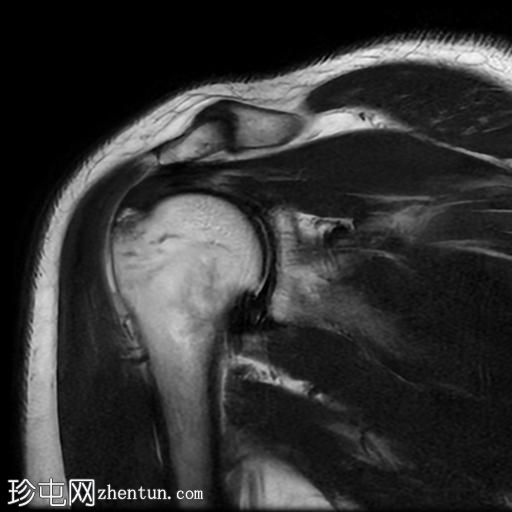

轴位PD序列

脂肪抑制序列

冈上肌腱关节面中前部纤维可见部分撕裂(边缘撕裂),伴局部骨髓水肿。

冈上肌腱关键区纤维以及冈下肌腱均可见肌腱病。

肩锁关节周围可见轻度关节囊肥厚和退行性改变。

此外,肩峰下滑囊内可见积液。

MRI 检查结果符合冈上肌腱的典型边缘撕裂,也称为部分关节面肌腱撕脱。